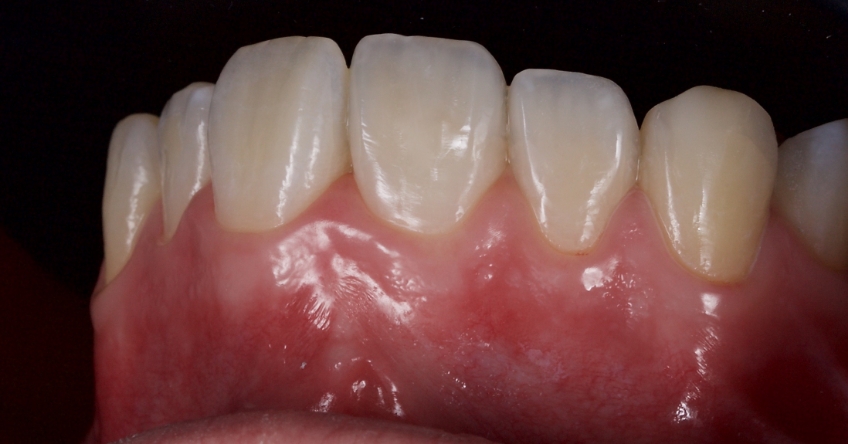

Any biofilm and aprismatic enamel were removed from the tooth, and the fragment was fragmented with light hydro abrasion with 29-micron alumina at 2-3 bar pressure. The tooth and the fragment were etched with 37% phosphoric acid (Ultradent), and a fourth-generation dentin bonding agent (Kerr, OptiBond FL) was applied (the adhesive component was not light-cured).

The fragment was luted to the tooth with heated chromatic enamel shade composite (GC G-aenial A2 shade). The heater used was a Calset Warmer from Addent. The excess composite was cleaned with an interproximal carver from American Eagle and smoothed with a number three brush and modeling resin (Brush & Sculpt from Cosmedent).

The composite was heated because it gained lower viscosity to improve adaptation. Plus, heating increases the conversion of monomer to polymer, which improves the physical characteristics of the resin, such as flexural strength and wear resistance, according to research by Da Costa, Hilton, and Swift in 2011.

The resin was polymerized, and the oxygen-inhibited layer was removed by polymerization under glycerine.

The enamel fracture on 2.1 was untouched and will be managed in conjunction with esthetic management of the white hypo calcification at a later time.